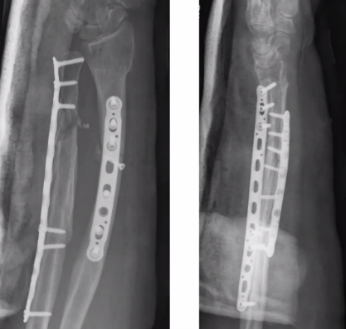

Q

65-årig kvinna

• Rökare, möjlig alkoholöverkonsumtion

• Tidigare kons beh distal radiusfraktur

• Ramlat över mattkant

• Sluten skada. NV intakt

Vad göra?

A

Plattan bra för att styra rotationskrafter, men direkt benläkning i radius och callusläkning i ulna